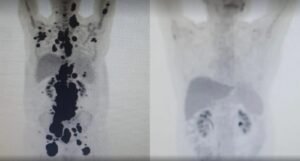

“A vitória não é só minha. É da fé, da ciência e da energia positiva das pessoas. Cada uma delas ajudou a colocar um paralelepípedo nesse caminho. A imagem prova com muita clareza para qualquer pessoa a gravidade do meu linfoma, e eu não tinha ideia de que era assim”, contou o paciente.

“Foi uma resposta muito rápida e com tanto tumor. Fico até emocionado [ao ver as duas ressonâncias de Paulo]. Fiquei muito surpreso de ver a resposta, porque a gente tem que esperar pelo menos um mês depois da infusão da célula. Quando a gente viu, todo mundo vibrou. Coloquei no grupo de professores titulares da USP e todo mundo impressionado de ver a resposta que ele teve”, comemorou o especialista.

Antes e depois

As duas imagens do Pet Scan (tomografia feita com um contraste especial) (veja acima) representam “dois Paulos”: a da esquerda, o paciente que tinha como caminho único os cuidados paliativos, quando a alternativa é dar conforto, mas já sem expectativa de cura, e a da direita, um paciente com um organismo já sem tumores após o tratamento com CAR-T Cell.